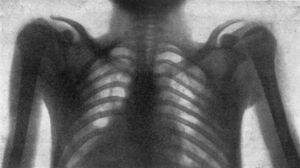

Evento 5 Aplicaciones desde 1895 hasta nuestros días de la radiación ionizante

Se realiza la primera radiografia de torax